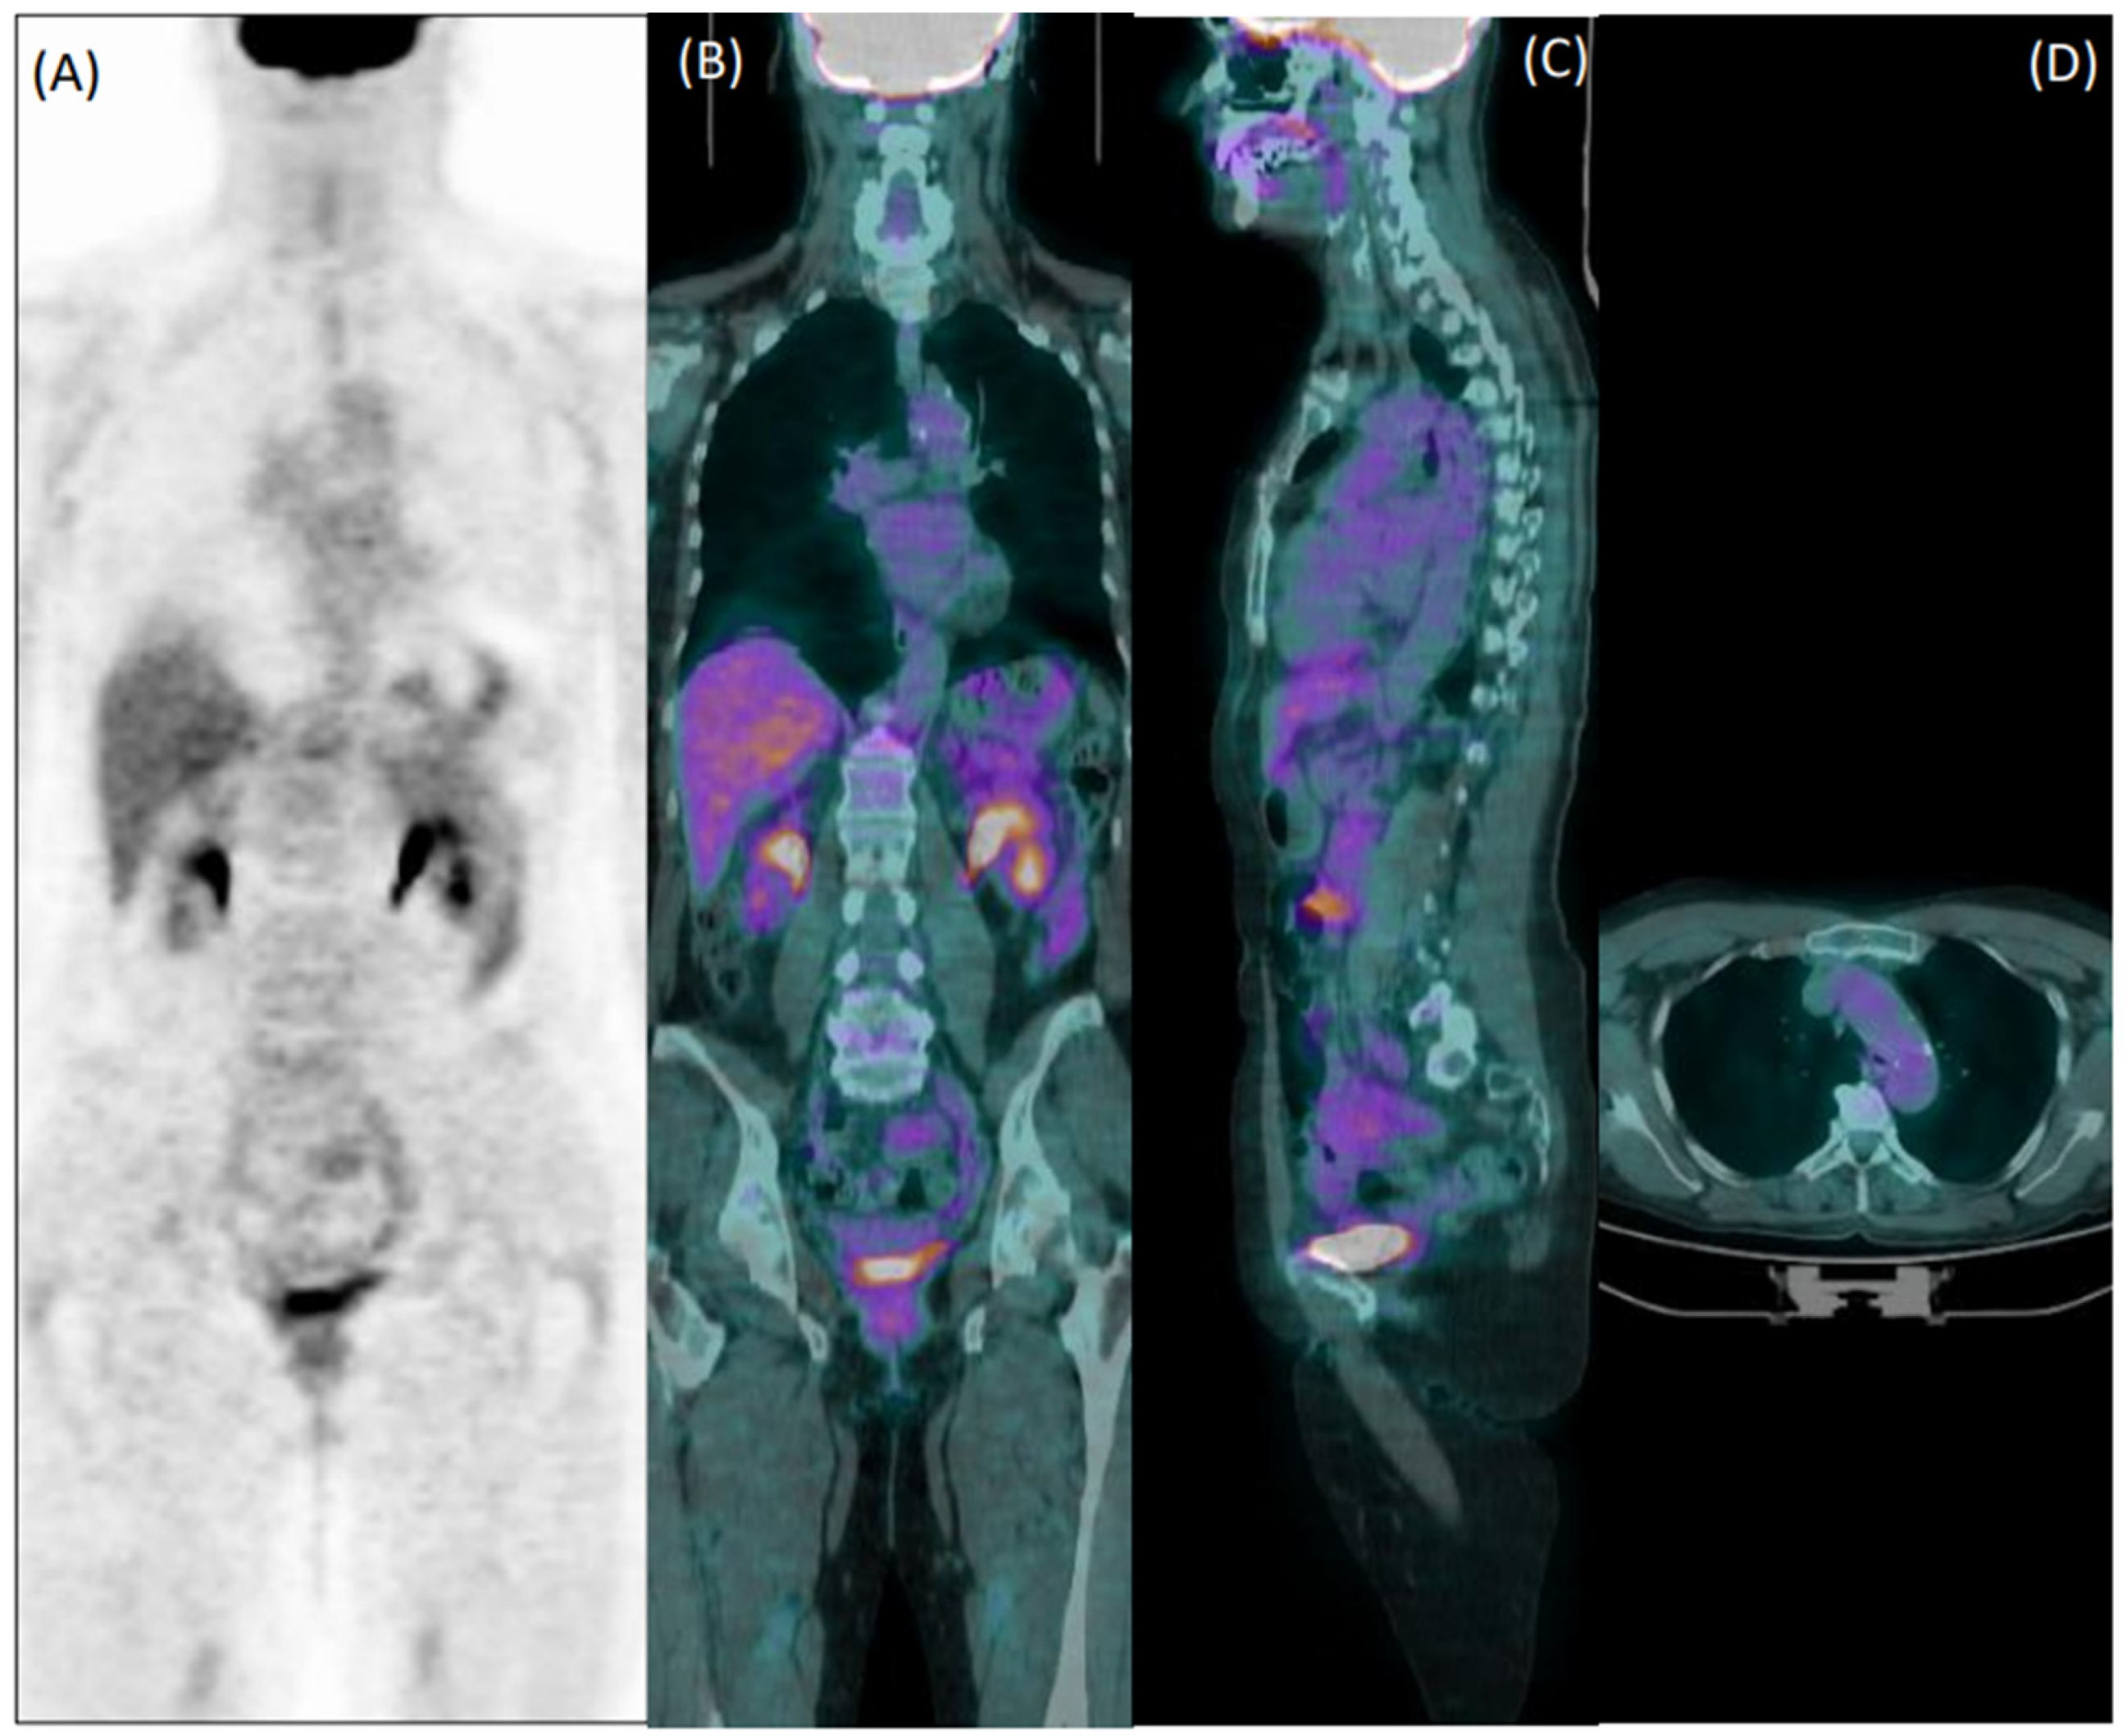

Collectively, 22/76 patients wrongly classified by reader 1 and 22/92 patients misclassified by reader 2 were elderly overweight patients who were taking steroids at the time of imaging. Figure 3 shows an example of a false negative PET exam during corticosteroid treatment.

Figure 3. Coronal [18F]FDG PET (A) and fused PET/CT coronal (B), sagittal (C), and axial (D) images of a 60-year-old female patient with giant cell arteritis, who performed the exam in the course of corticosteroid therapy. Both readers evaluated images as negative for arteritis.